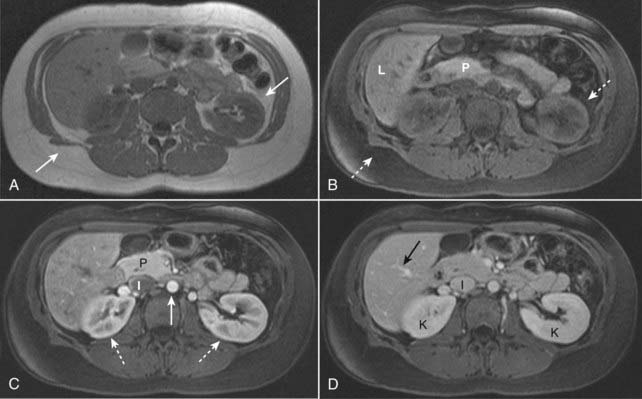

Figure 20-10 Fat suppression and normal enhancement of the abdomen following the administration of intravenous gadolinium.

A, T1-weighted image of a normal abdomen demonstrates normal bright subcutaneous and intraabdominal fat (solid white arrows). B, T1-weighted, fat-suppressed image shows that the signal from the fat has been suppressed (dotted white arrows) and is now dark. Intraabdominal organs such as the pancreas (P) and liver (L) now appear brighter relative to the adjacent suppressed fat. C, T1-weighted, fat-suppressed, early phase post-gadolinium image shows the normal enhancement of the aorta (solid white arrow) which enhances earlier than the inferior vena cava (I). The kidneys demonstrate normal corticomedullary phase enhancement (dotted white arrows), and the pancreas (P) enhances maximally during this phase. D, T1-weighted, fat-suppressed, later phase post-gadolinium image shows that the hepatic veins (solid black arrow) and inferior vena cava (I) are now well enhanced. The kidneys (K) now demonstrate normal homogeneous enhancement, the optimal phase to detect renal masses.